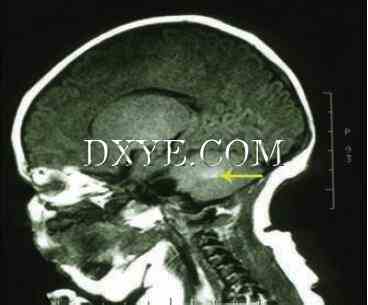

对于那些患有神经性皮肤黑色素沉着症的高风险患者,建议对CNS进行磁共振成像(MRI)筛查。 MRI应该在大脑正常髓鞘形成之前在生命早期(4至6个月龄之间)进行,这将掩盖黑色素沉积物的可视化。图20.1显示了患有神经性皮肤黑色素沉着症的患者的典型MRI。脑脊液细胞学也可用于分析非典型恶性细胞的存在。

图 20.1.&#8194; MRI扫描患有涉及躯干和下肢的巨型先天性色素沉着痣的患者,发现其在脑小脑中具有无症状焦点黑斑病(箭头)。由于脑膜性黑色素沉着症的症状无症状,并且患者遵循常规的神经逻辑检查,因此皮肤先天性色素沉着痣重现的计划没有改变。